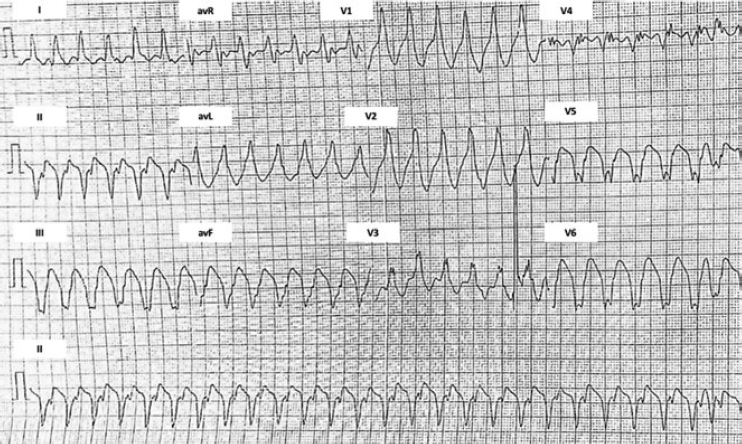

This is the case of a 51-year old male without a past medical history. One month before his admission he experienced fast heart palpitations associated with diaphoresis, nausea and vomit. Both the electrocardiogram and the Holter monitor showed recurring episodes of monomorphic ventricular tachycardia (figure 1). The physical examination confirmed the presence of an aortic ejection murmur exacerbated when performing the Valsalva maneuver. The transthoracic echocardiography showed obstructive asymmetric septal hypertrophy with a 32-mm maximum septal diameter (figure 2A), a 65-mmHg gradient in the left ventricular outflow tract, and systolic anterior motion of the mitral valve with moderate regurgitation. The cardiovascular magnetic resonance imaging confirmed the presence of extensive myocardial fibrosis as a risk factor of sudden death (figure 2B and video 1 of the supplementary data). Amiodarone and propranolol were prescribed, and an automatic defibrillator was implanted as a secondary prevention measure. The patient was readmitted to the hospital 4 months later with signs of electrical storm with multiple discharges provided by the device implanted. Deep sedation, mechanical ventilation, and hemodynamic support were administered, and the stellate ganglion was blocked. However, the patient progression was poor with persistent episodes of ventricular tachycardia that triggered the mapping of cardiac electrophysiology using the CARTO 3 system (Biosense Webster, Israel). The ablation of a septal macroreentrant circuit of the left ventricle associated with the clinical ventricular tachycardia was unsuccessful (figure 2C).

Figure 1. Initial electrocardiogram. Ventricular tachycardia originated at the mid-inferior septum of the left ventricle.